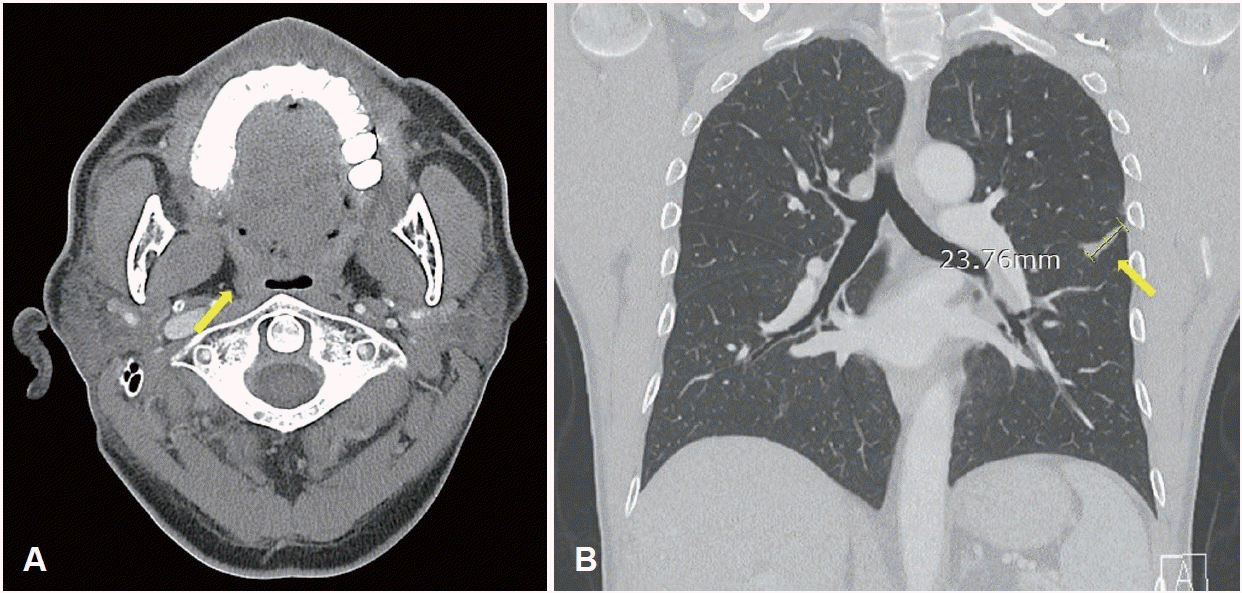

Contrast-enhanced neck CT showed a peripherally enhancing lesion with central low attenuation (1.8 cm) in the right palatine tonsil (Fig. 2A), and neck MRI showed a lobulated mass (2.3 cm) at the same site with low T1 signal intensity and intermediate T2 signal intensity (Fig. 2B). There was no local invasion and there were no notable findings in the cervical lymph nodes.

Radiologic findings. A: Contrast-enhanced neck CT showing a 1.8-cm peripherally enhancing, centrally low-density lesion in the right palatine tonsil (yellow arrow). B: Neck MRI showing a 2.3-cm lobulated mass in the right palatine (yellow arrow) tonsil with intermediate T2 signal intensity. C: Chest CT showing a 3.8-cm lobulated mass (yellow arrow) extending across the left major fissure and involving the adjacent pleura. D: PET-CT demonstrating fluorodeoxyglucose uptake in the right palatine tonsil (yellow arrow, SUVmax 21.64), left lower lobe lung lesion (blue arrow, SUVmax 26.41), left hilar lymph node (blue arrow, SUVmax 29.64), and small intestine (green arrow, SUVmax 16.55).

After the second course of radiotherapy during treatment, neck CT showed disappearance of the right tonsillar lesion, and radiotherapy was concluded while immunotherapy was continued. After three cycles of immunotherapy, neck CT showed no residual lesion in the right tonsil (Fig. 4A), and chest CT showed marked reduction in the size of the left primary lung cancer and the metastatic hilar lymph node (Fig. 4B). Abdominal CT also showed resolution of the small bowel lesion previously identified. On outpatient endoscopic re-evaluation, the ulcerative mass previously observed in the right tonsil had resolved and no active mass was identified (Fig. 5). The patient is currently being followed while maintaining immunotherapy.

Post-treatment radiologic assessment following CCRT. A: Follow-up neck CT showing no residual enhancing mass in the right palatine tonsil (yellow arrow). B: Follow-up chest CT showing a decreased size of the previously noted lobulated mass (yellow arrow) extending across the left major f issure.